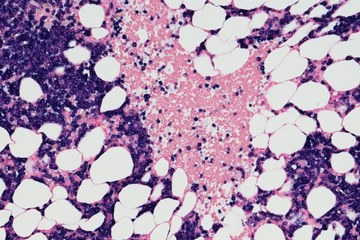

An image of multiple myeloma cells

HOPA News Late Breaking News

Late-Breaking HOPA News: Redefining Relapse: What MajesTEC-3 Means for the Treatment of Multiple Myeloma

Sanja Zepcan, PharmD, BCPS, BCOP, and Emily Rux, PharmD, BCOP, discuss the clinical questions raised by the recent MajesTEC-3 trial and the potential changes it finds in the treatment of multiple myeloma.